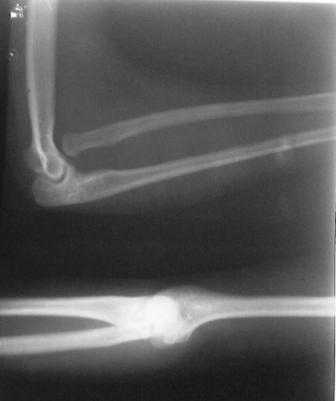

Врожденный вывых головки лучевой кости |

Обратилась девушка 18-лет, с жалобами на деформации обоих локтевых суставов, больна с рождения.

Оба локтевых сустава в положении сгибания под углом 145гр., дальше разгибание нет за счет укороченных и натянутых м/тканей по передне-наружной поверхности л/сустава. Сгибание полное. но при сгибание предплечья супинируется а при разгибание пронируется,при фиксированным п/плечье ротационных движений нет.Со стороны костно-суставной системы других обл. я патологию не находил. В 2001 г. оперирована лев.рука в одном из центральном институте, со слов вывых был вправлен открыто и фиксация аппаратом Илизарова, после операции рука не сгибалась и ротационных движений не было, что очень ей мещало, после усиленных ЛФК наступило релюксация и движение стало лучше, т.е. как прежная. Фото и Р-снимки прилагается.